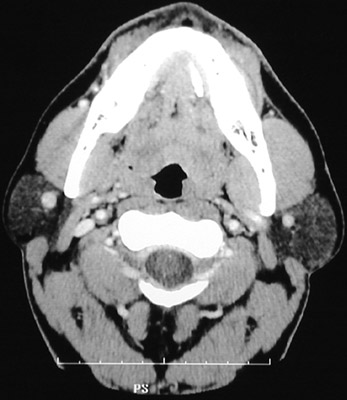

There is a bright calculus seen in the left distal submandibular salivary gland duct extending upward to the floor of the mouth from the gland located below the mandible in this head CT scan. (The parotid gland on each side is normal.)